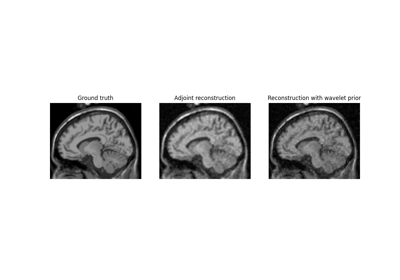

Examples using mrinufft.operators.autodiff.DeepInvPhyNufft#

Model-based iterative reconstruction